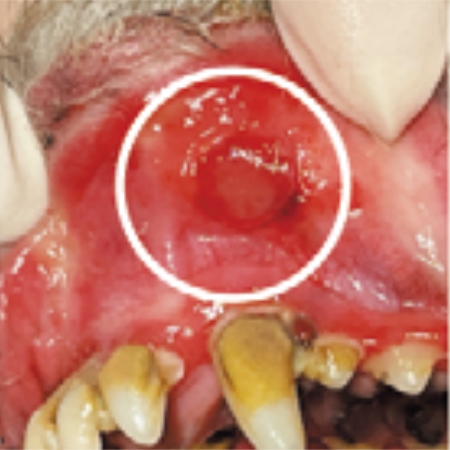

人と同じように、犬にも口内炎ができます。口の中の粘膜が炎症を起こし、赤くなったり、ただれたりするほか、出血したりします。犬では、進行した歯周病に続発して起きることが多いとされています。

口の中にあらわれる症状

口内炎の原因になっている腎臓病や糖尿病、自己免疫疾患などの基礎疾患が見つかれば、それに合った治療を優先して行います。歯周病があれば、歯垢・歯石の除去手術を行うことに加え、抜歯が必要になる場合もあります。